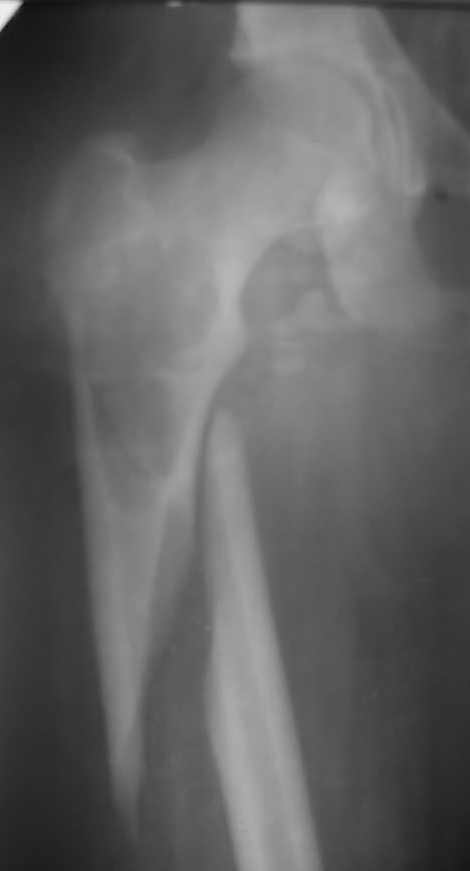

[Ortho] Патологический перелом бедренной кости.

Здравствуйте уважаемые коллеги , Посоветуйте, пожалуйста, тактику лечения (метод

фиксации) патологического перелома бедренной кости у пациента 16- ти лет. С уважением.